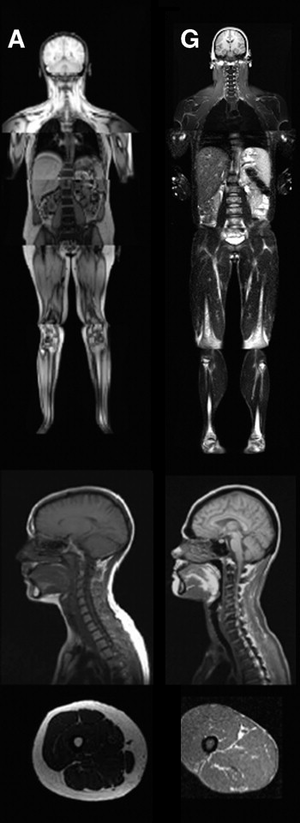

MRI of control patient vs. diseased patient.

An MRI image illustrating the lack of subcutaneous fat of a patient with the disease (G) compared to a control patient (A).